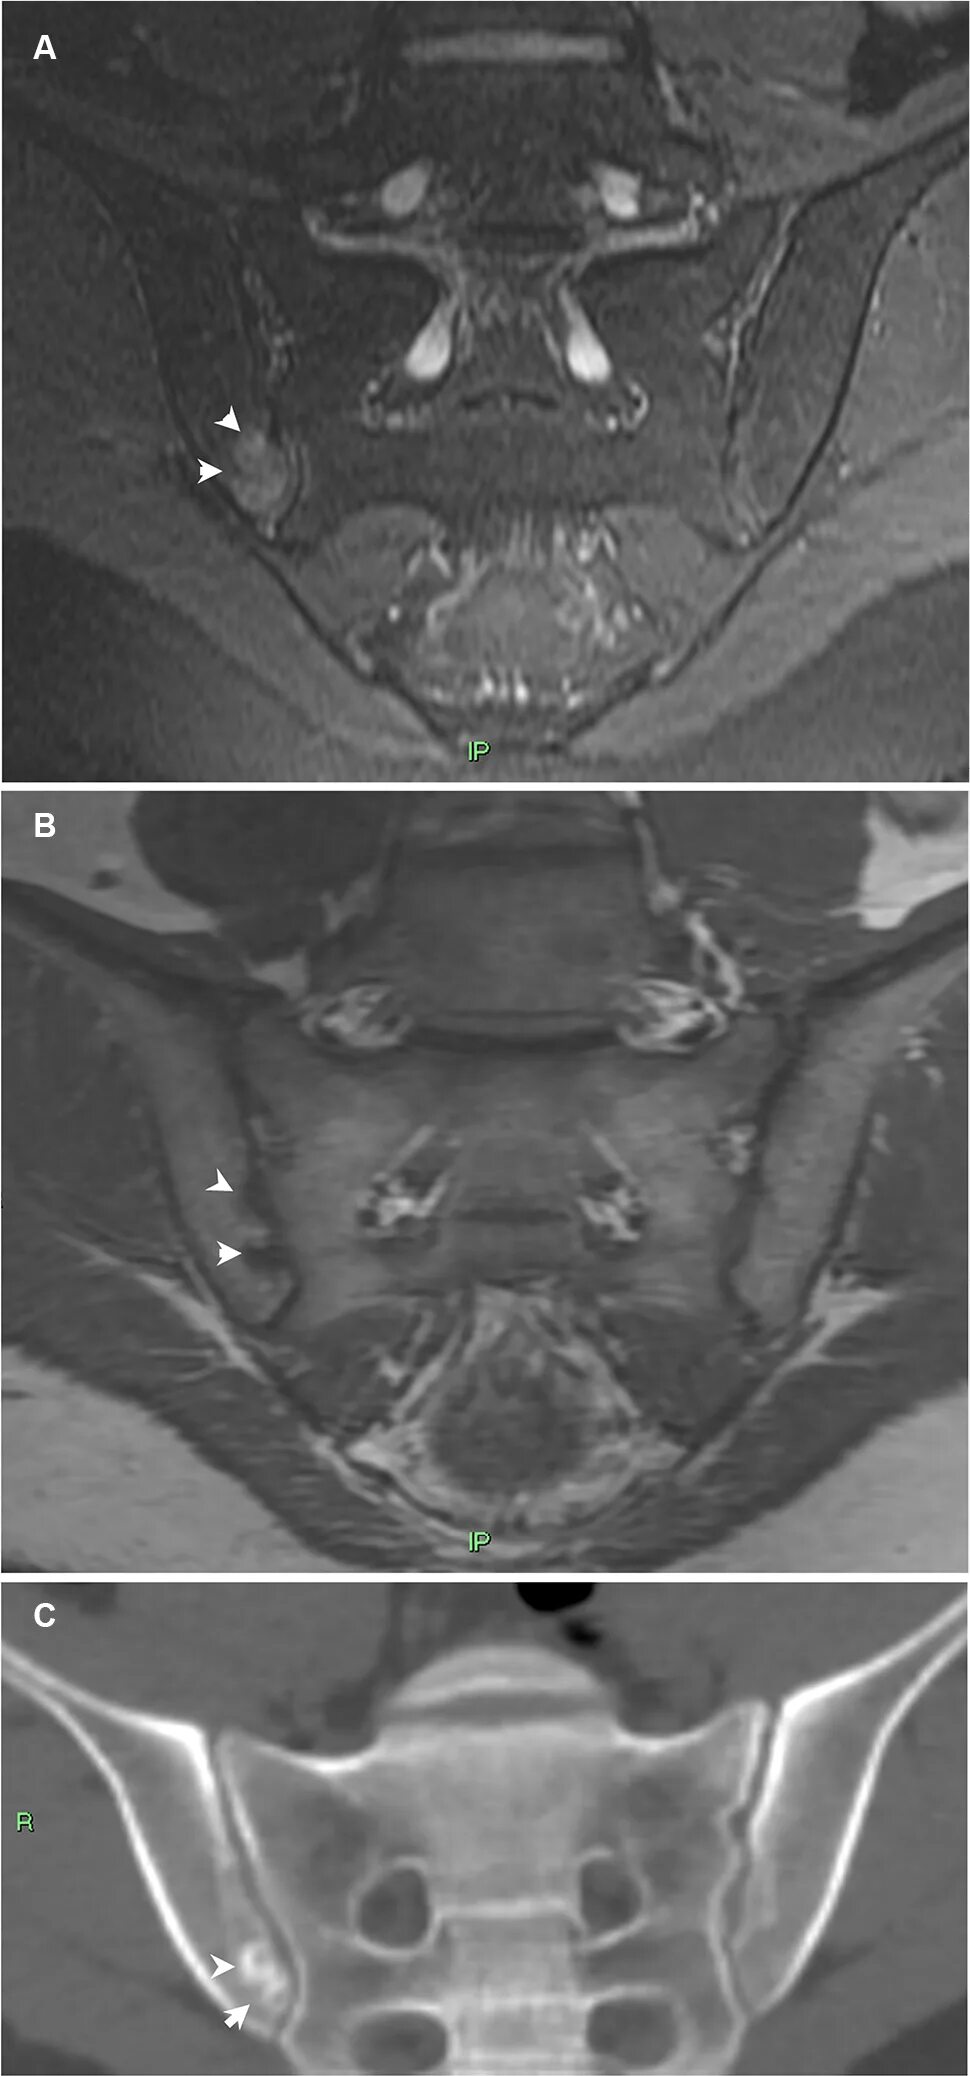

Сакроилеит на кт